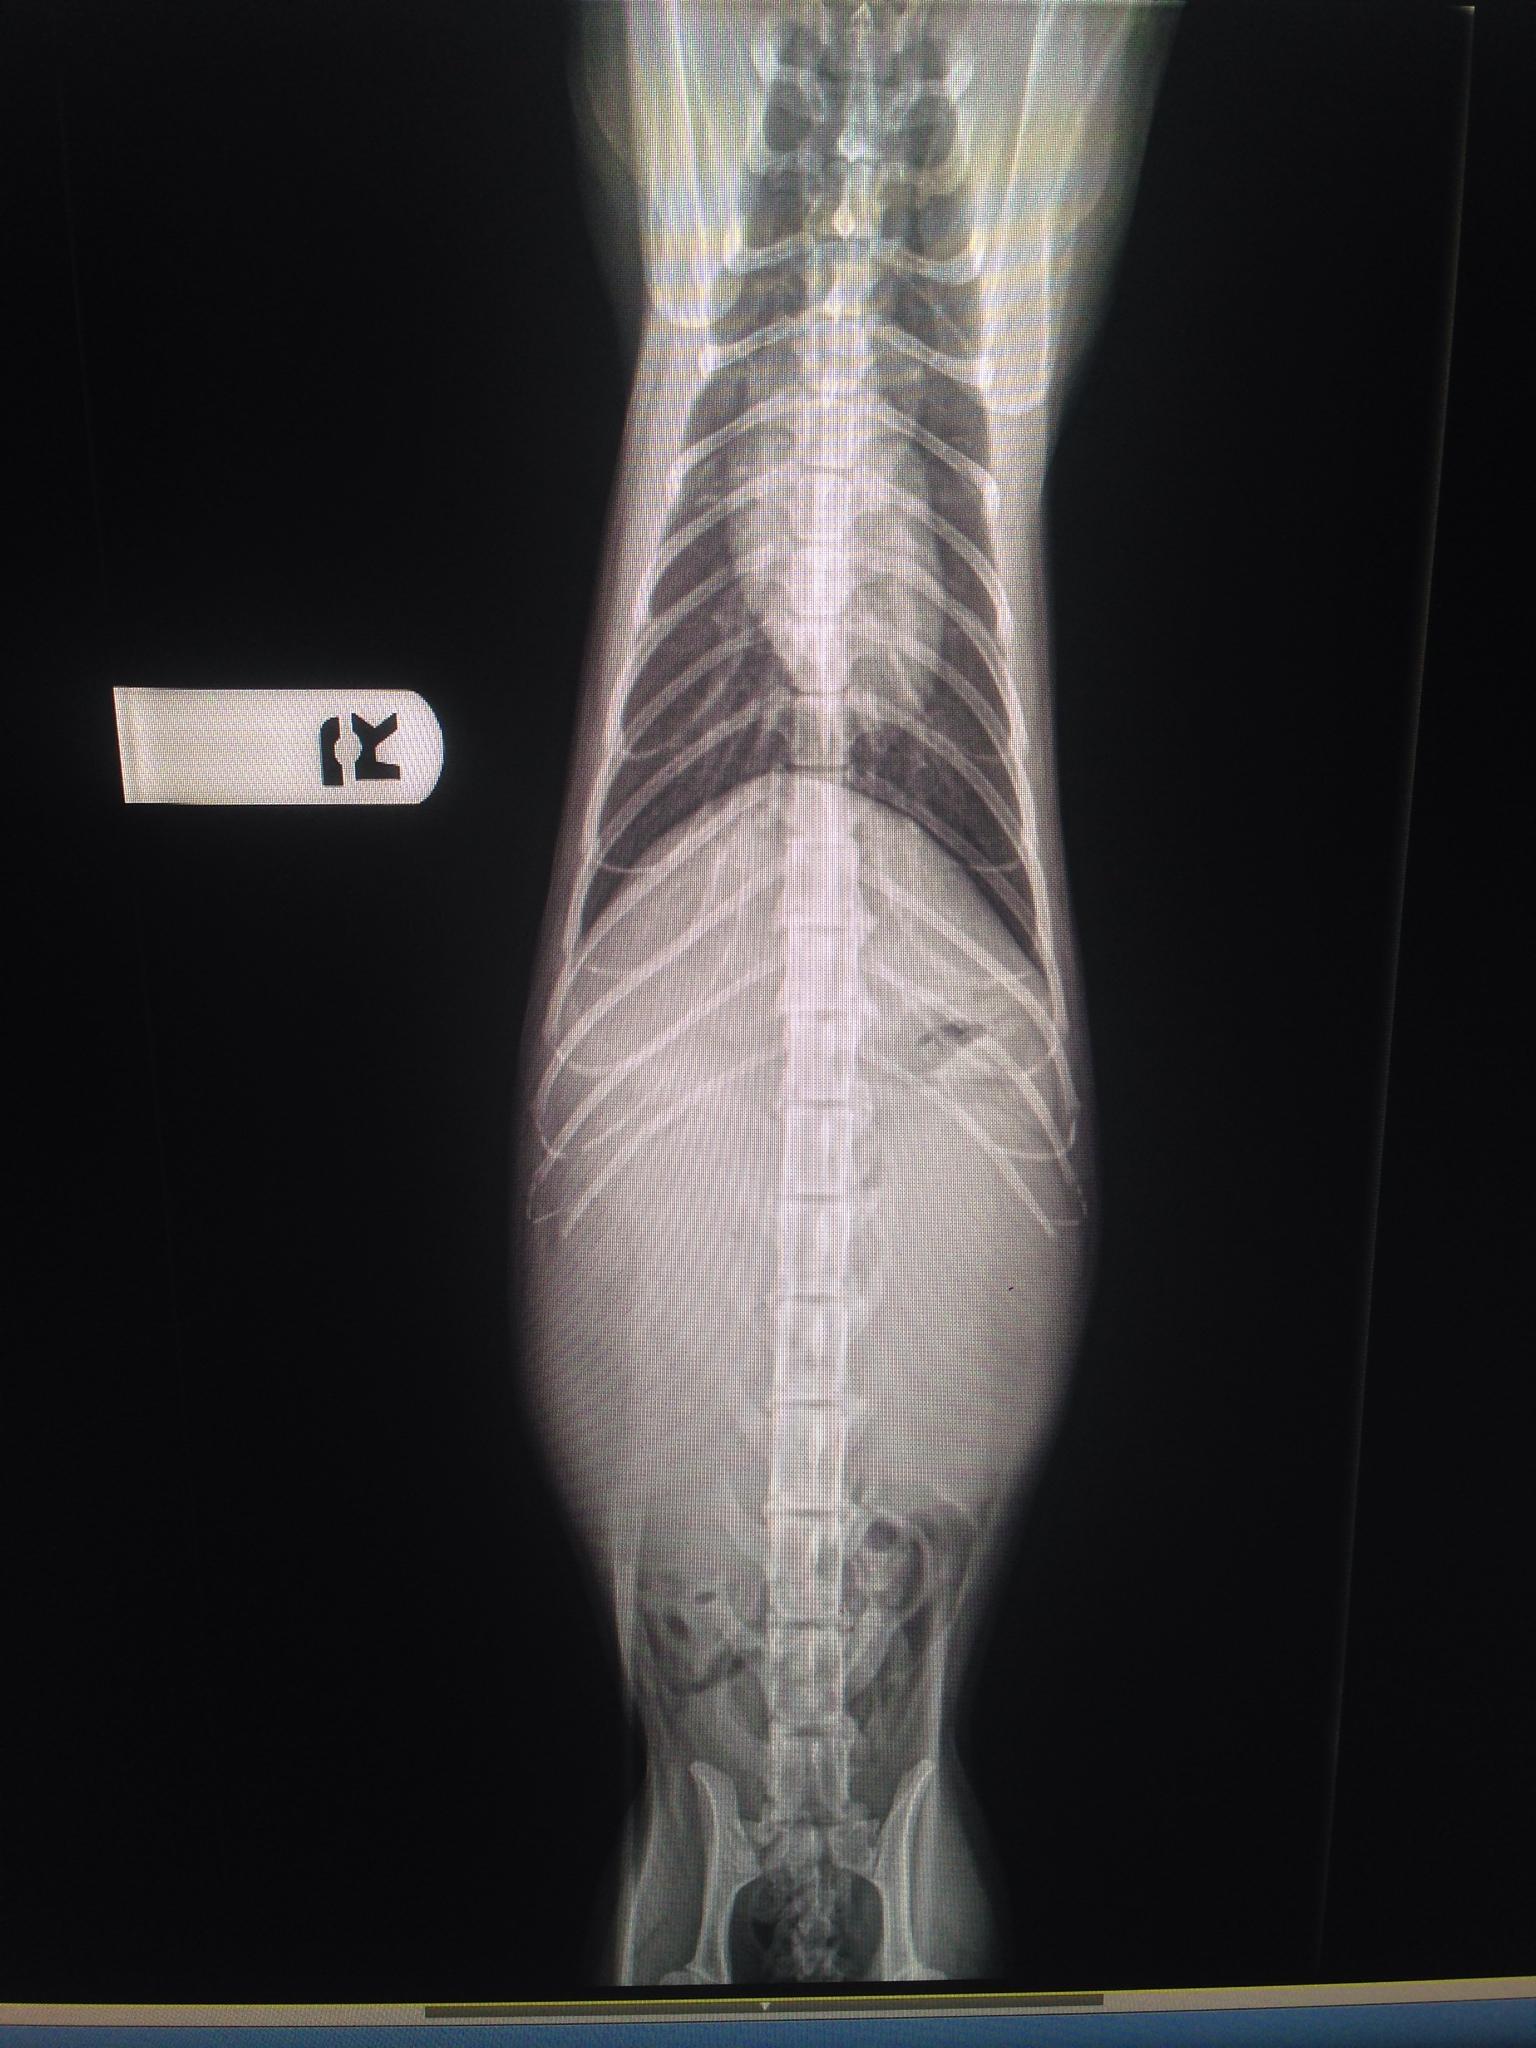

Renal lymphoma in a 10 year old MN DSH cat with renomegaly

A 10-year-old NM DSH was presented for evaluation of renomegaly. Urinalysis showed low SG (1.015) and proteinuria. Azotemia was present in the serum biochemistry.

Bilateral renomegaly: lymphoma, hydronephrosis, pyelonephritis, peri-nephric cysts, polycystic kidney disease.

Image Interpretation

The kidneys were bilaterally enlarged with cortical striations and loss of corticomedullary definition. Both kidneys presented subcapsular capping (thin hypoechoic line below renal capsule) with fluid accumulation or proliferative neoplastic tissue. The right kidney measured 6.7 cm. The left kidney measured 6.8 cm.